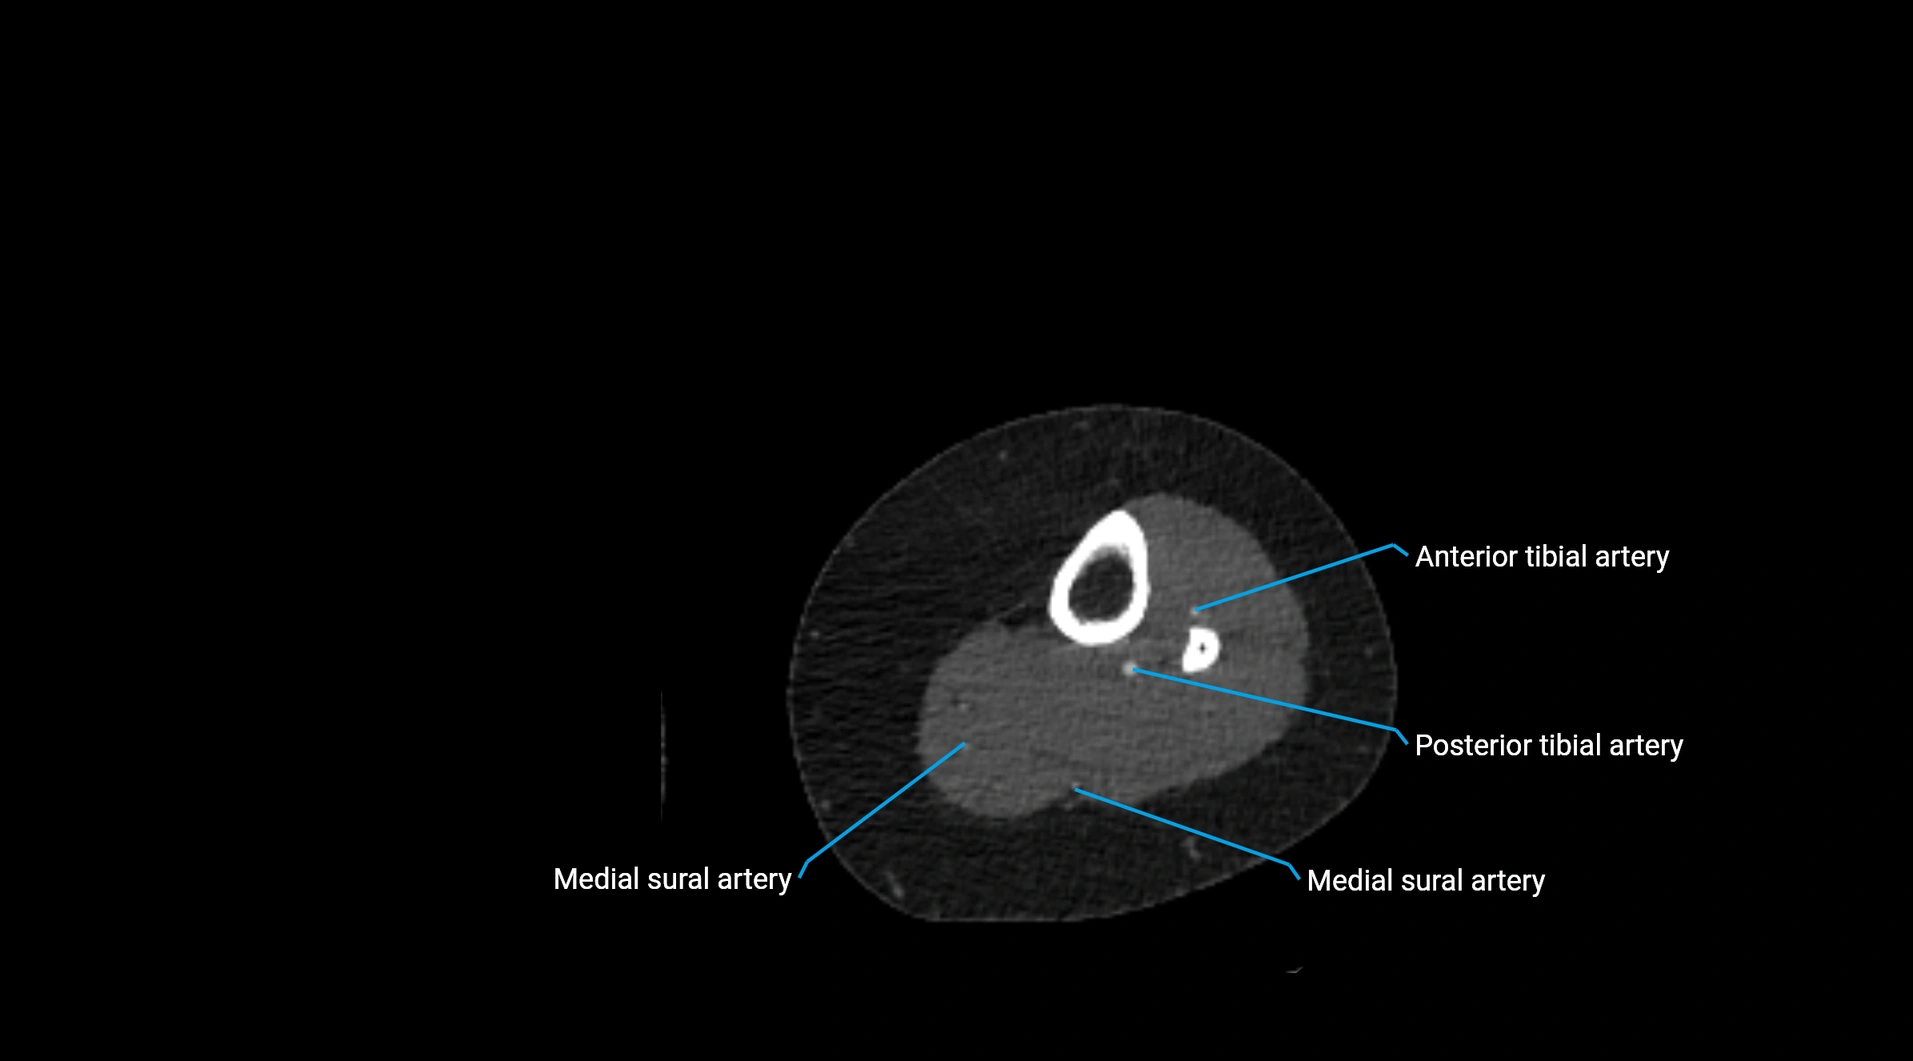

MRI images

image